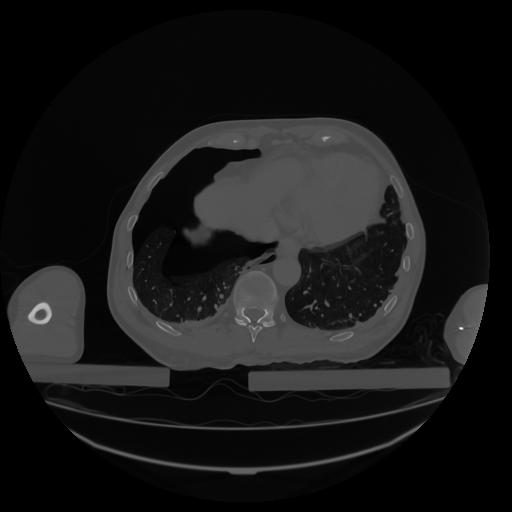

34 CUERPO,CE,Vol,1.0,CUERPO,,